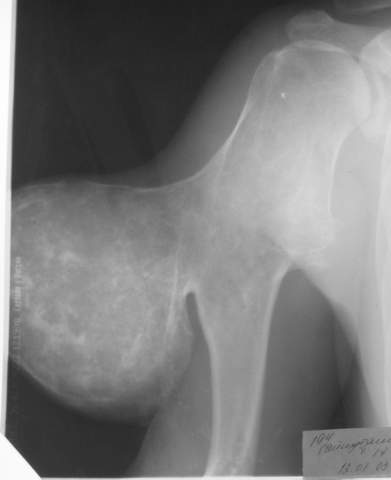

Вот, пришел сегодня утром на работу,фотоаппарат зачем то прихватил.ни о чем таком не думал,а там такоое...:-)

Мужчина, 27 лет, IQ вроде бы нормальный, из района, но не из деревни, а такую штуковину вырастил... аж жуть...

А каков Ваш диагноз?

По-моему больше всего похоже на вторичную хондросаркому (озлокачествленный костно-хрящевой экзостоз плеча).

Похоже

Что это озлокачествленный экзостоз - очевидно...

Но тактика лечения при любых раскладах одна - удалять.

О метастазах при таких хондросаркомах я нигде не читал.

Значит другого лечения не требуется...

Окромя наблюдения.

Skoree vsego хондросаркомa вторичнaя, na osnove Multiple osteochondomatosis.